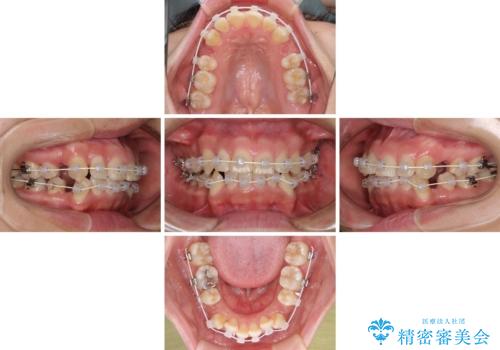

- 矯正装置

- 審美装置

- 上下前歯のデコボコを気にして来院された患者様です。

デコボコが強いため、非抜歯で矯正をすると出っ歯仕上がりとなるため、上下左右の第一小臼歯4本を抜歯することとしました。

当初予定は2年半程度と伝えていましたが、2年にも満たない期間で治療を終えることができました。